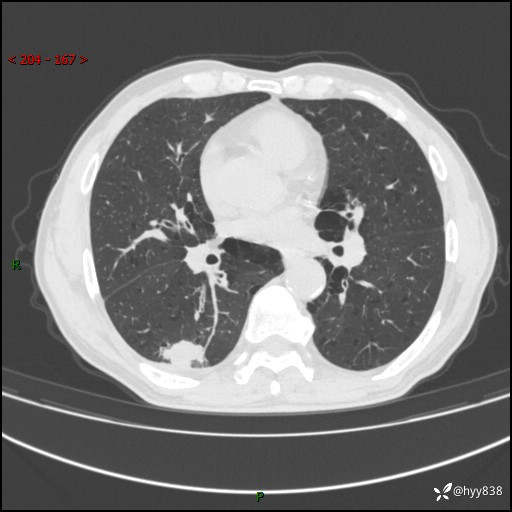

老年男性,发现右下肺结节3天。结节+卫星灶,似曾相识---结果公布~

主诉:发现右下肺结节3天

简要病史:患者3天前于我院常规体检时行胸部CT提示“右下肺结节35mm*24mm”,自觉无发热、咳嗽、咳痰,无胸痛、咯血、气促加重,无声嘶、吞咽困难,无乏力、盗汗、体重减轻等不适。为求进一步诊治,入我院求诊,门诊以“右下肺结节待查”收入我科。患者3天前于我院常规体检时行胸部CT提示“右下肺结节35mm*24mm”,自觉无发热、咳嗽、咳痰,无胸痛、咯血、气促加重,无声嘶、吞咽困难,无乏力、盗汗、体重减轻等不适。为求进一步诊治,入我院求诊,门诊以“右下肺结节待查”收入我科。 起病以来,患者精神、食欲、睡眠可,体力稍差,大小便正常,体重无明显变化。

辅助检查:CT

临床诊断:肺结节

胸部CT平扫